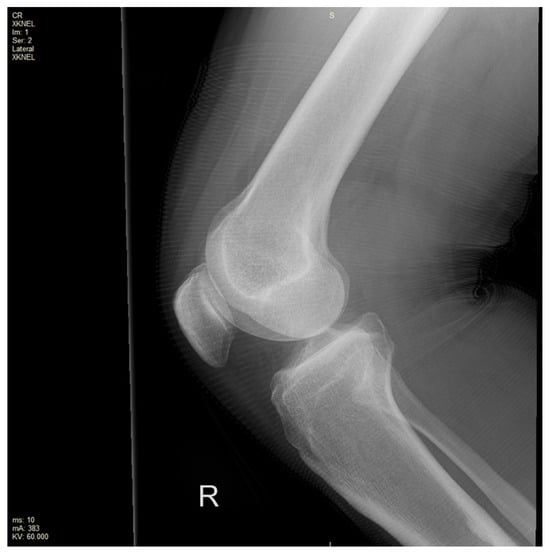

Anterior Cruciate Ligament Rupture with Concurrent Gastrocnemius Tear: A Case Report of a Rare Pattern of Injury

Background, Clinical Significance: Anterior cruciate ligament (ACL) injuries are common, however the occurrence of concurrent gastrocnemius muscle tears is exceptionally rare. Given this, the diagnosis and management of this pattern of injury is poorly characterised, with lack of current clinically relevant classification systems and evidence-based guidelines to guide treatment. Early recognition is essential. with advanced imaging critical to guiding the diagnosis and management of patients with this pattern of injury. Case presentation: A 39 year old man presented with acute right knee swelling, pain and difficulty weightbearing following a sports-related fall. Clinical examination was suspicious for an ACL injury. Magnetic Resonance Imaging (MRI) of the knee demonstrated the disrupted and displaced ACL fibres, with extensive peri-cruciate oedema around the expected position of the ACL. It was associated with partial avulsion of the medial gastrocnemius origin and incomplete avulsion of the lateral gastrocnemius origin. The patient was referred for an urgent orthopaedics review and is currently on trial of conservative management. Conclusions: In this case report and review of the literature, we evaluate the current understanding of the complexities of combined musculoskeletal injuries and limitations of existing classifications in providing accurate diagnosis and management strategies. Given the rarity of this presentation, the case underscores the lack of evidence-based recommendations for early management, particularly in young, active individuals who are at risk of significant long-term functional impact. Full article